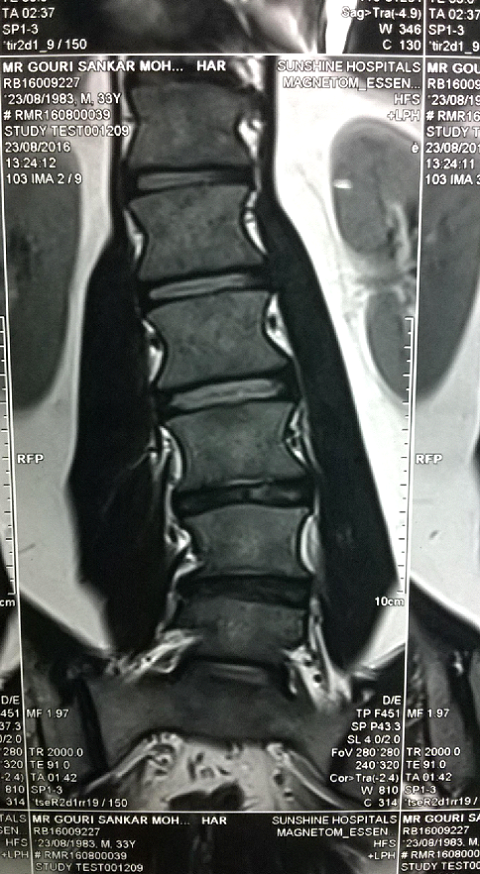

MRI of Gouri Shankar Mohapatra